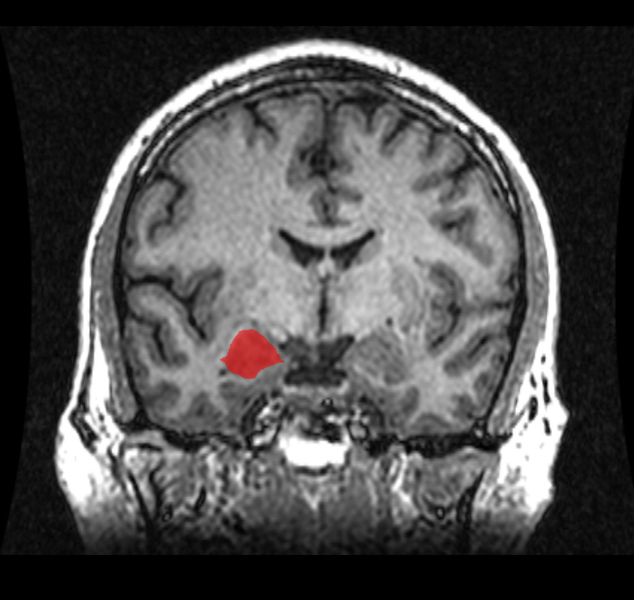

75 persen massa otak adalah cairan dalam bentuk darah. Otak menerima energi dari darah. Saat darah sedang memompa, otak akan gemuk.

Saat tidur, berbagai bagian otak mati, dan konsumsi energi yang berkurang mengurangi pembengkakan di neuron. Retakan darah otak, menciptakan ruang kosong yang besar.

Inilah yang terjadi selanjutnya di otak yang membuat tidur sangat vital bagi kelangsungan hidup.

Otak adalah sebuah organ pendaur ulang limbah yang luar biasa. Tanpa tidur, racun menumpuk dan membunuh kita setelah sekitar 200 jam.